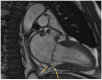

Valvular heart disease is a leading cause of cardiovascular morbidity and mortality and a major contributor of symptoms and functional disability. Knowledge of valvular heart disease epidemiology and a deep comprehension of the geographical and temporal trends are crucial for clinical advances and the formulation of effective health policy for primary and secondary prevention. This review mainly focuses on the epidemiology of primary (organic, related to the valve itself) valvular disease and its management, especially emphasizing the importance of heart valve centers in ensuring the best care of patients through a multidisciplinary team.